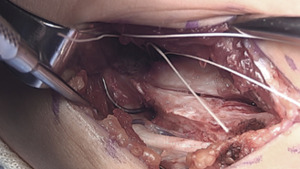

Closure

The proximal tunnel lateralized typically leaves a good cuff of the native ligament to sew over the top of the brace/graft. A 2-0 vicryl suture is utilized here in a figure-of-eight fashion. A 2-0 fiber wire suture is then used more distally, bringing together the arms of the tendon graft, native ligament, and internal brace.

The wound is copiously irrigated. The posterior raphe is closed with a running 2-0 vicryl suture.